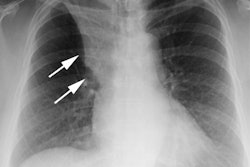

- X-ray: